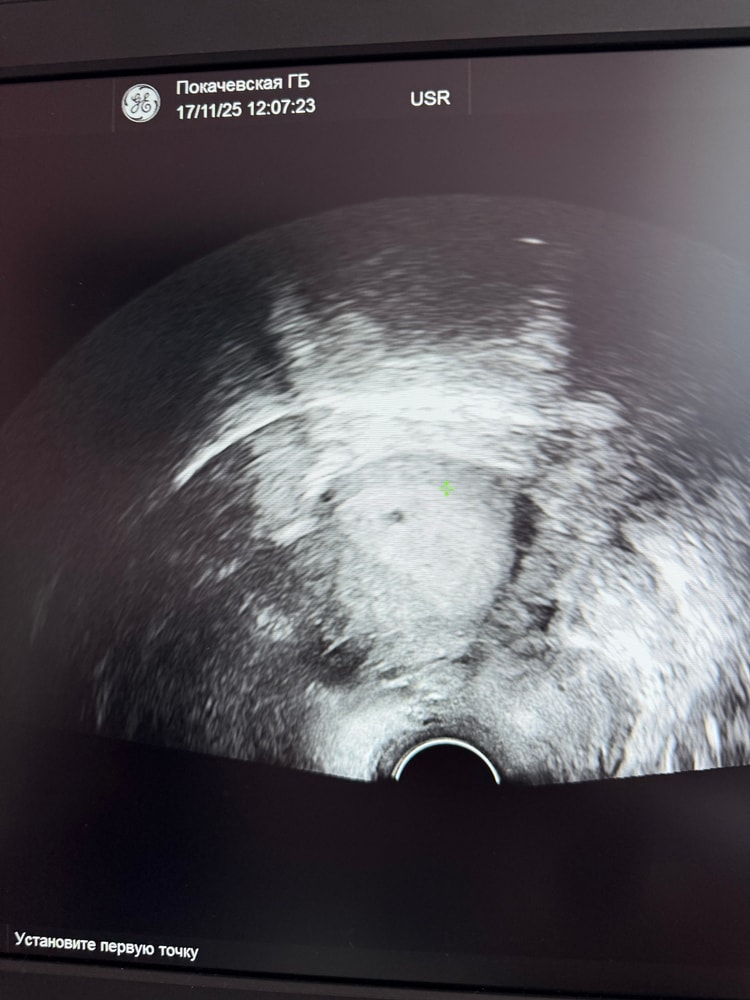

17.11 отписываюсь. Была на узи сегодня 17.11- в матке плодное яйцо, пока что маленькое, сб нет еще. Контроль через 10 дней)